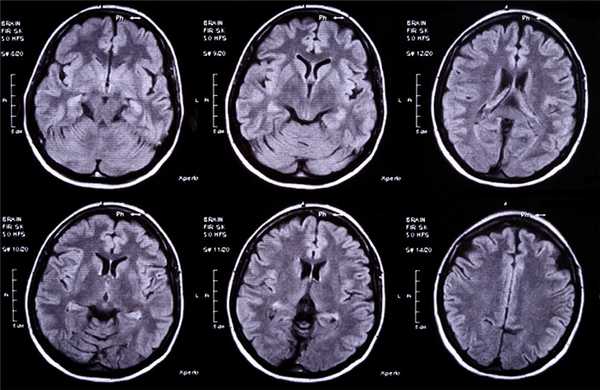

Абсцесс левого полушария мозжечка, выявленный при магнитно-резонансной томографии головного мозга в T1 C+ режиме на аксиальном срезе.

Абсцесс левого полушария мозжечка, выявленный при магнитно-резонансной томографии головного мозга в T2 режиме на аксиальном срезе.

Абсцесс левого полушария мозжечка и расширение боковых желудочков, выявленные при магнитно-резонансной томографии головного мозга в T1 C+ режиме на коронарном срезе.

Магнитно-резонансная томография (МРТ) проводится при подозрении на абсцесс головного мозга.

МРТ головного мозга — более точный метод диагностирования. При проведении МРТ на первых стадиях формирования абсцесса мозга (1-9 сутки) энцефалитический очаг выглядит: на Т1-взвешенных изображениях — гипоинтенсивным, на Т2-взвешенных изображениях — гиперинтенсивным. МРТ на поздней (капсулированной) стадии абсцесса головного мозга: на Т1-взвешенных изображениях абсцесс выглядит, как зона пониженного сигнала в центре и на периферии (в зоне отека), а по контуру капсулы сигнал гиперинтенсивный. На Т2-взвешенных изображениях центр абсцесса изо- или гипоинтенсивный, в периферической зоне (зоне отека) гиперинтенсивный. Контур капсулы четко очерчен.

Для того чтобы провести точную диагностику места расположения абсцесса мозга и мозжечка, проводят компьютерную и магнитно-резонансную томографию головного мозга. При проведении компьютерной томографии выявляется тонкая, гладкая стенка абсцесса, которая имеет правильные контуры. Магнитно-резонансная томография позволяет также определить капсулу абсцесса. Если нет возможности провести вышеперечисленные виды исследования, можно провести пневмоэнцефалографию или радиоизотопную сцинтиграфию головного мозга.